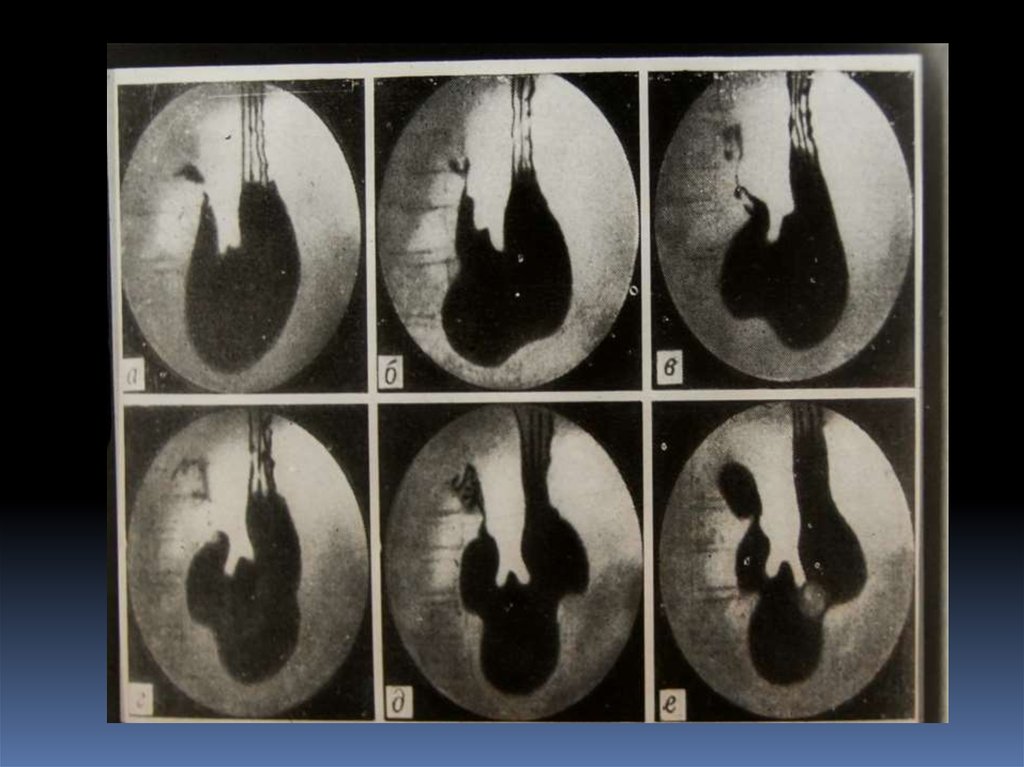

17. Классификация рака органов ЖКТ

1. Экзофитная форма:

2. Эндофитная форма:

узловая форма;

диффузноинфильтративная

форма;

полипоподобная

чашеподобная форма. инфильтративноязвенная.

3. СМЕШАННАЯ ФОРМА – 10-15%